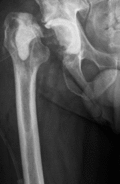

Procedere: Nach der entsprechenden Vorbereitung erfolgte im September der Ausbau der McMinn-Prothese sowie die Resektion des Schenkelhalses, ein Débridement im Bereich des Hüftgelenkes sowie die Einlage eines Spacers (i.S. einer Copal Zementeinlage) in die Hüftpfanne und im Bereich des proximalen Femurschaftes (Girdlestone Situation). Ende November 2017 erfolgte 6 Wochen nach Spacer Implantation (Abbildung 2) eine erneute Wiedervorstellung zur Punktion des Hüftgelenkes als Vorbereitung auf den Prothesenwiedereinbau. Hierbei wurde erneut ein E. coli detektiert und eine antibiogrammgerechte Antibiose mittels Ciprofloxacin 500mg 1-0-1 fortgesetzte. Die Indikation zum Spacerwechsel wurde gestellt. Der Eingriff konnte geplant Anfang Dezember durchgeführt werden.

Ende Dezember erfolgte die erste Punktion des Hüftgelenkes, bei der schließlich kein Keimnachweis erfolgte. Nach 6 weiteren Wochen konnte ebenfalls kein Keim mehr im Hüftgelenk nachgewiesen werden, so dass für März 2018 der Hüft-TEP-Wiedereinbau geplant wurde. Bei der Vorbereitung und Planung (CT Diagnostik) zeigte sich ein relativ großer knöcherner Defekt im Bereich des kranialen Acetabelums, sodass mit einem Burch-Schneider- Ring (Abbildung 3) geplant wurde.